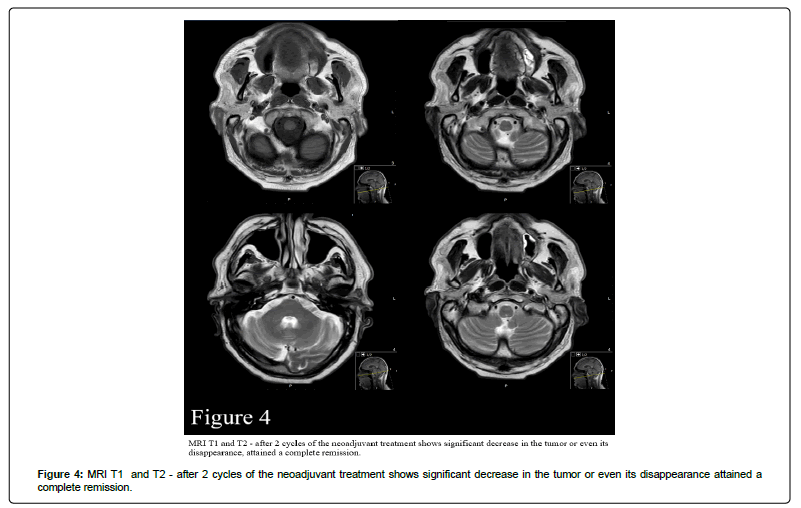

The MRI scan after 3 cycles revealed a significant decrease in the tumor or even its disappearance, and on examination WHEN? The patient had attained a complete remission in the clinic examination (Figure 4, Figure 5).

Figure 4: MRI T1 and T2 - after 2 cycles of the neoadjuvant treatment shows significant decrease in the tumor or even its disappearance attained a complete remission.